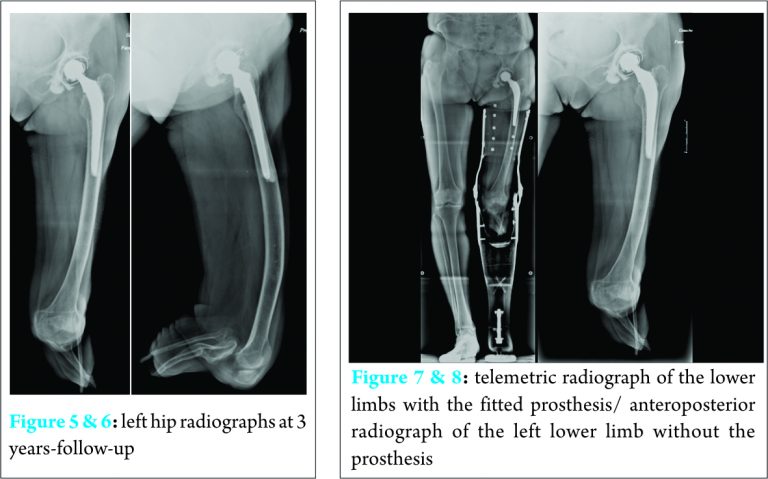

The functional outcome was good with a Harris Hips score at 87/100, and a Paustel-Merle-D’Aubigné at 16/18. The left hip radiographs did not reveal any signs of loosening or migration of the femoral and acetabular implants, neither signs of polyethylene wear (Fig. 5, 6 & 7).